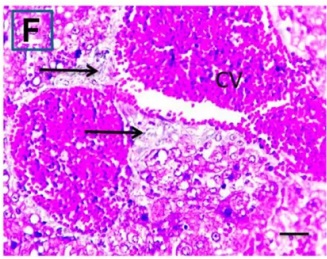

Put the liver tissue section under a microscope, and you can see that cisplatin can cause liver congestion (the blood that should return to the heart is blocked and stagnates in the hepatic veins), cell degeneration (vacuoles appear, which is the earliest change in cellular injury), apoptosis and necrosis, but these conditions can also be alleviated by using Ganoderma lucidum.

Figure 2 Effects of cisplatin and Ganoderma lucidum on hepatocytes